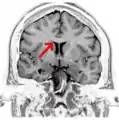

Corpus callosum

The corpus callosum (Latin for "tough body"), also callosal commissure, is a wide, thick nerve tract, consisting of a flat bundle of commissural fibers, beneath the cerebral cortex in the brain. The corpus callosum is only found in placental mammals.[1] It spans part of the longitudinal fissure, connecting the left and right cerebral hemispheres, enabling communication between them. It is the largest white matter structure in the human brain, about 10 in (250 mm) in length and consisting of 200300 million axonal projections.[2][3]